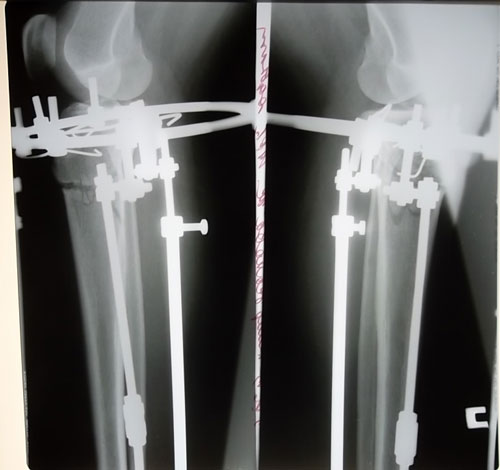

- Диагноз: О-образная деформация ног

- Диагноз: о-образная деформация нижних конечностей